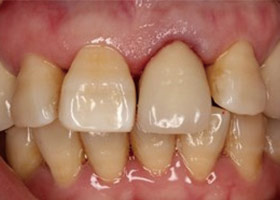

治療前全口X光片、口內正面照片。

治療前門牙特寫、切端特寫照,發現假牙略微暴牙。